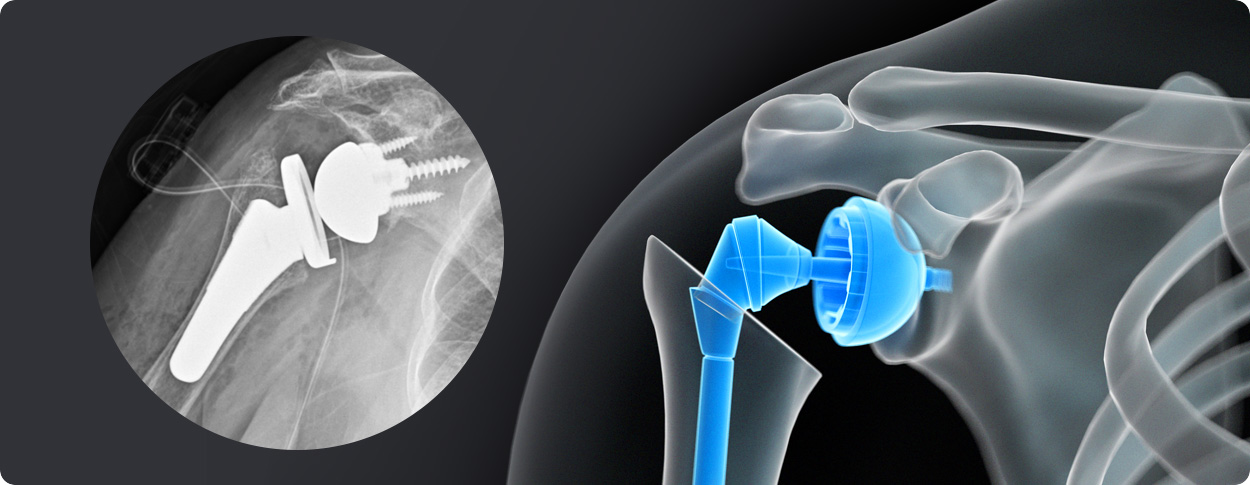

삼하게 망가져 거의 기능이 없는 관절을 제거한 후 특수하게 제작된 인공관절을 삽입하는 수술

역행성 인공관절 전치환술

역행성 인공관절 진치환술

(회전근개 심한 파열 및 관절염 진행)